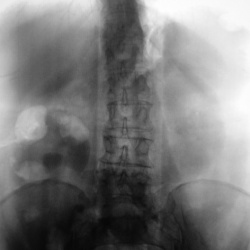

Мужчина. 60 лет. Поступал в клинику с якобы левосторонней почечной коликой. УЗИсты дают двусторонний гидронефроз и камень в н\трети правого мочеточника. Проведена обзорная и в\в урография. Ваше...

Пациент направлен на внутривенную урографию. Диагноз - "Мочекаменная болезнь?". Врач УЗИ сообщил, что "камни" с обеих сторон. По поводу картины сильно не распространялся.

Внутривенная урография. Пациент направлен из военкомата.Жалоб пациент не предъявляет. Произведено стандартное исследование.